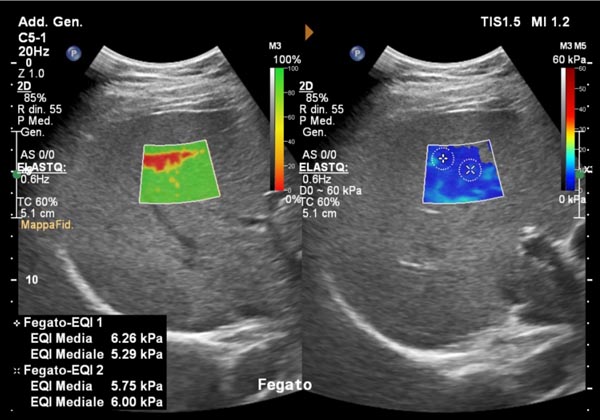

Elastosonografia del fegato: una valida alternativa alla biopsia?

Una delle applicazioni più importanti è la valutazione della fibrosi epatica.Il fegato, in presenza di infiammazioni croniche come le epatiti virali o la steatosi, può sviluppare fibrosi, cioè una sostituzione del tessuto sano con tessuto cicatriziale più rigido.«L’elastosonografia shear wave ci consente di stimare la rigidità del fegato senza ricorrere alla biopsia epatica — spiega il dott. Ivona — offrendo una stima affidabile e ripetibile nel tempo».Questo permette di monitorare l’evoluzione della malattia, valutare l’efficacia delle terapie e individuare precocemente i pazienti a rischio di cirrosi, riducendo l’uso di procedure invasive.

L’esame è indicato per chi soffre di epatite cronica B o C, steatosi epatica, epatopatie alcoliche o patologie autoimmuni del fegato.